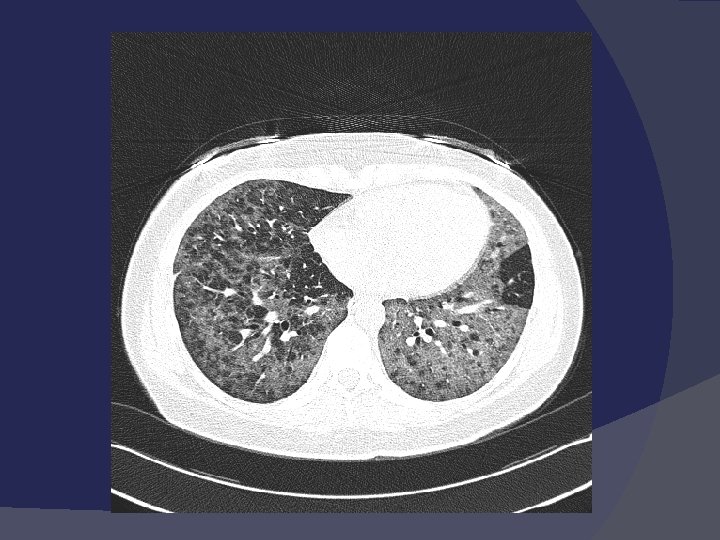

Компьютерная томография Может быть использована при малосимптомных вариантах течения пневмонии, так как обладает в 2 раза более высокой чувствительностью при выявлении очагов инфильтрации. Необходима для дифференциальной диагностики.

Компьютерная томография